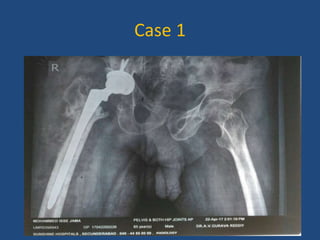

Case 1